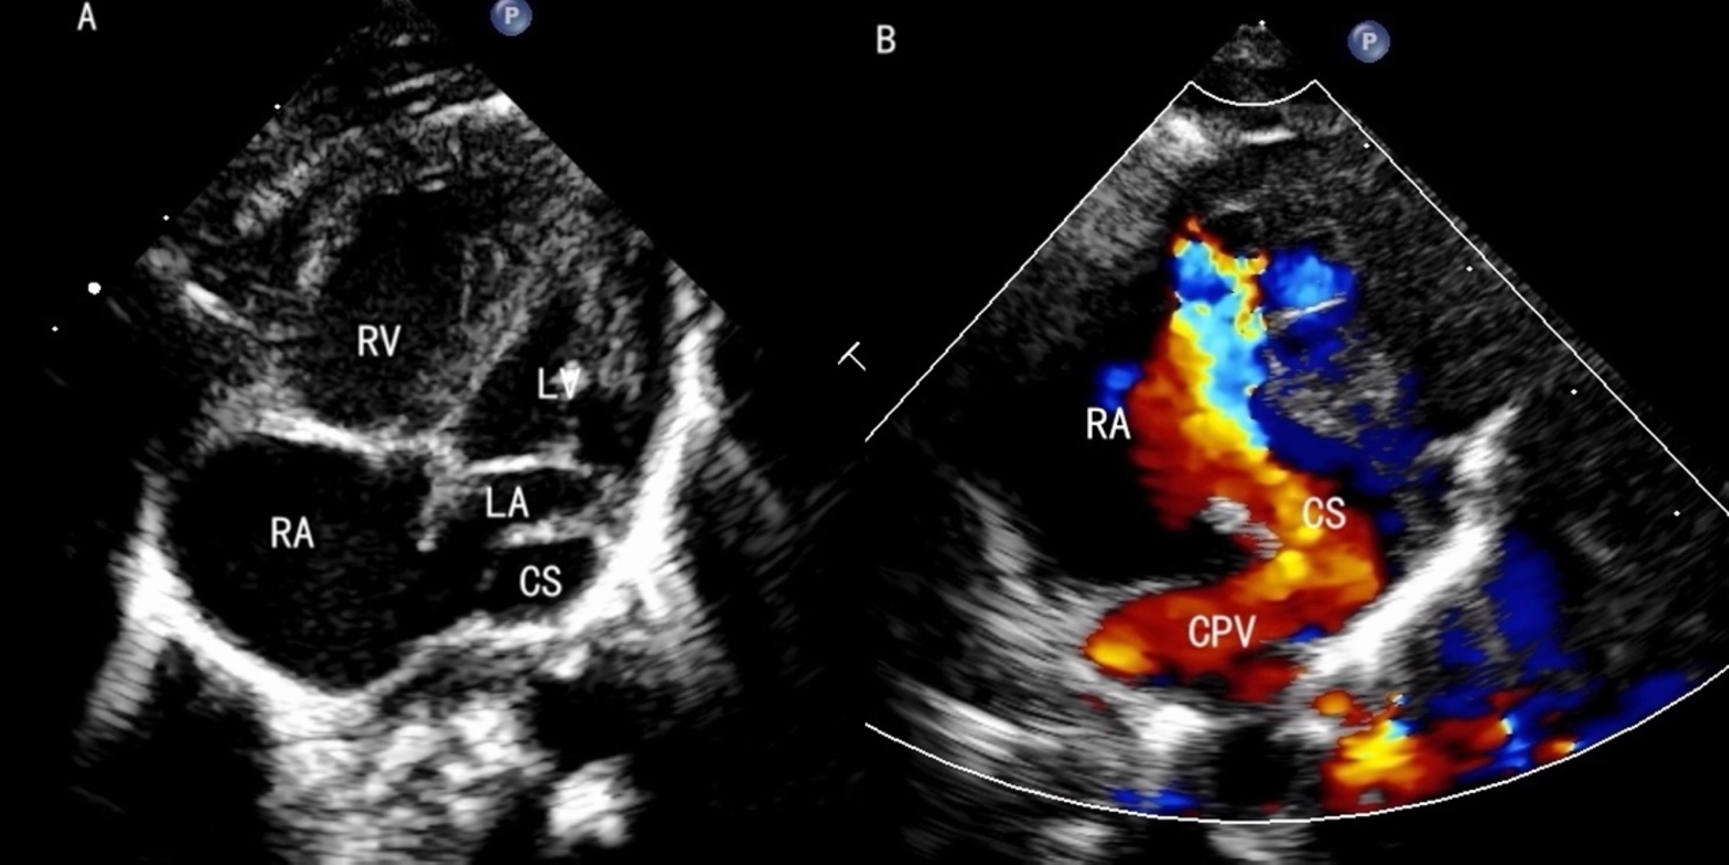

The echocardiography of cardiac TAPVC. (A) The CS is dilated behind the small LA. (B) The CPV drains into the CS.